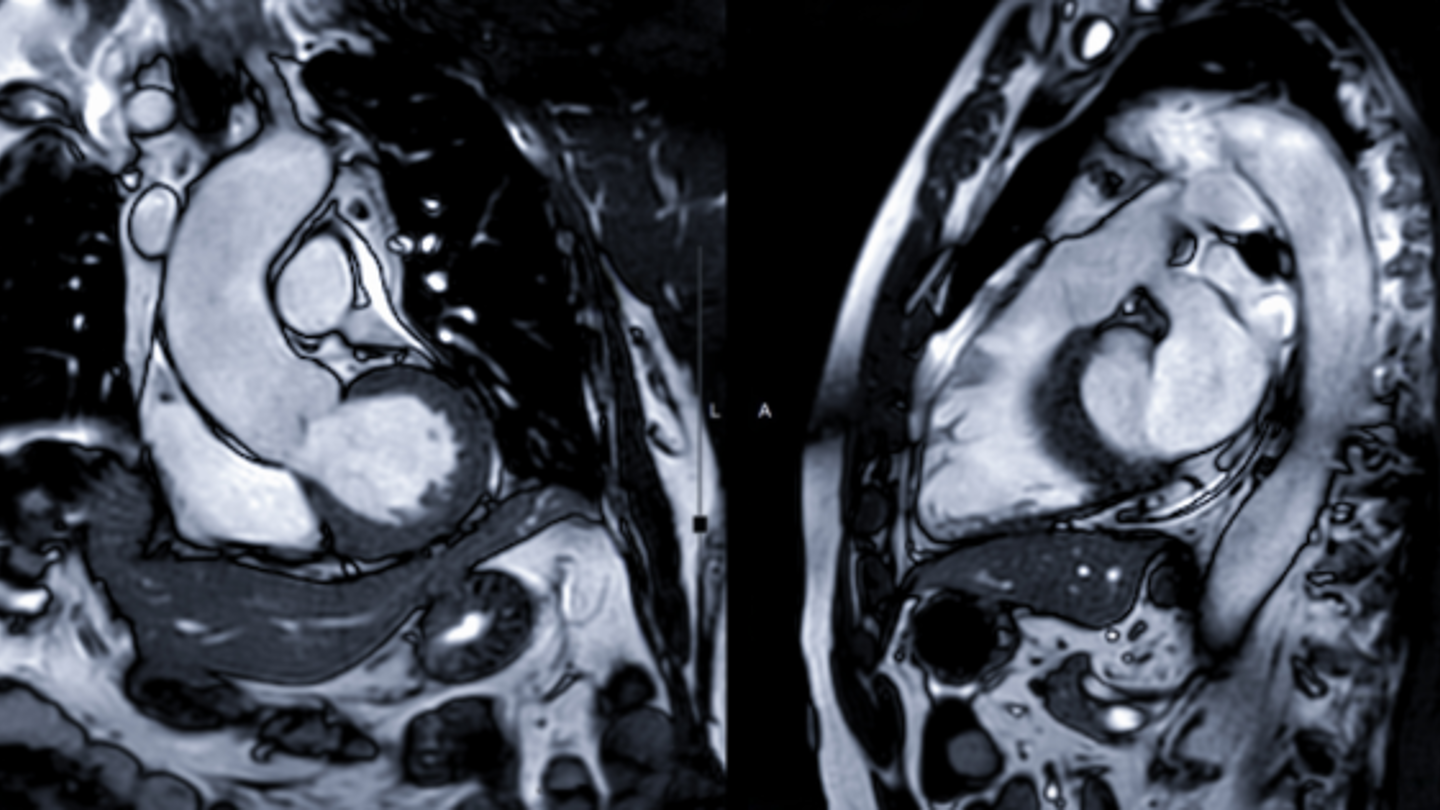

Cardiac MRI scans

We offer cardiac MRI scans with reports returned from highly experienced Cardiac Consultant Radiologists within 3 working days. A cardiac MRI scan allows cardiologists to view exceptionally detailed images of your internal organs, including your heart structure and blood vessels.

MRI stands for magnetic resonance imaging. It allows you to take pictures of your body by using a strong magnetic field and radio frequency pulses. A cardiac MRI scan produces images of the heart muscle and valves and is used to assess both its structure and function.

What can a Cardiac MRI scan show?

- Assess the structure and function of your heart chambers, valves, and major blood vessels.

- Diagnose cardiovascular problems such as cancers, tumours and inflammatory conditions.

- Detect the blockage of blood vessels

Image slices are taken during the scan while the MRI moves across three planes:

- Sagittal - From side to side

- Axial - From top to bottom

- Coronal - From front to back